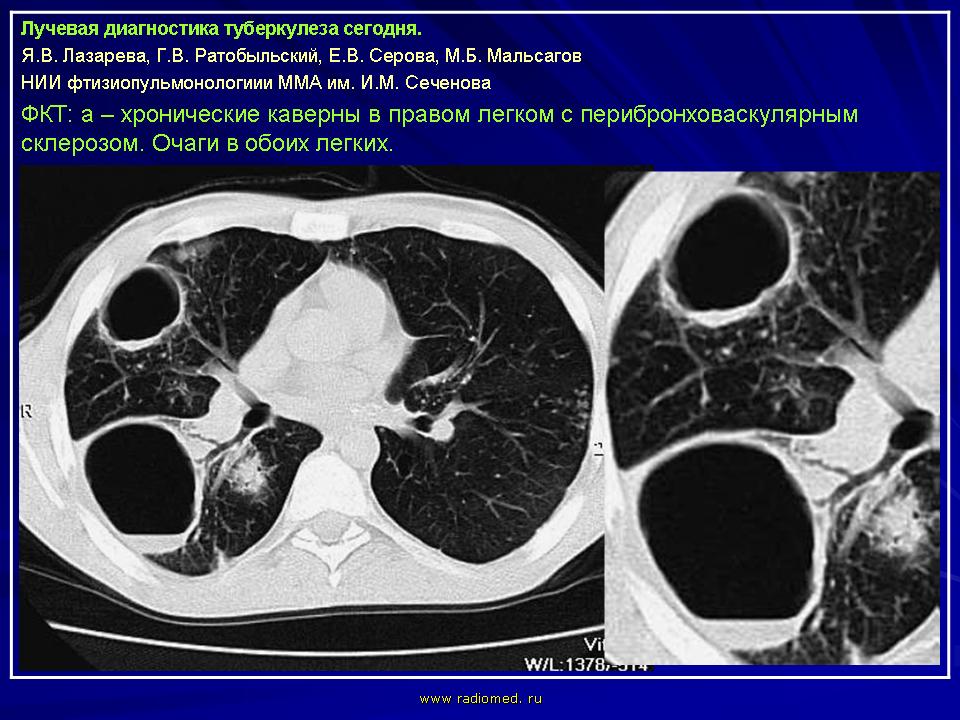

Лучевая диагностика туберкулеза сегодня

Я.В. Лазарева, Г.В. Ратобыльский, Е.В. Серова, М.Б. Мальсагов

НИИ фтизиопульмонологиии ММА им. И.М. Сеченова